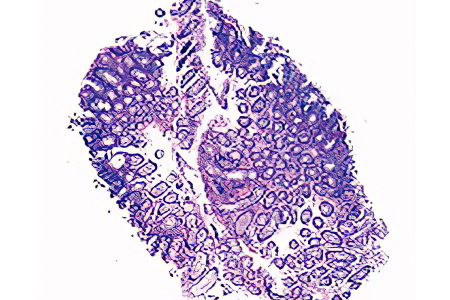

Скрытая кровь в кале — это кровь, которую невозможно выявить ни визуально, ни при микроскопическом анализе испражнений. Обнаружить её можно только с помощью анализа на скрытую кровь. Положительный результат указывает на наличие скрытого желудочно-кишечного кровотечения и требует дальнейшего обследования пациента.

Анализ кала на скрытую кровь является важным диагностическим инструментом, который позволяет выявить наличие кровотечений в желудочно-кишечном тракте. Врачи отмечают, что этот тест может помочь в ранней диагностике различных заболеваний, включая язвы, полипы и рак кишечника. Поскольку скрытая кровь может быть признаком серьезных патологий, важно проводить этот анализ регулярно, особенно для людей старше 50 лет или тех, кто имеет предрасположенность к заболеваниям ЖКТ.